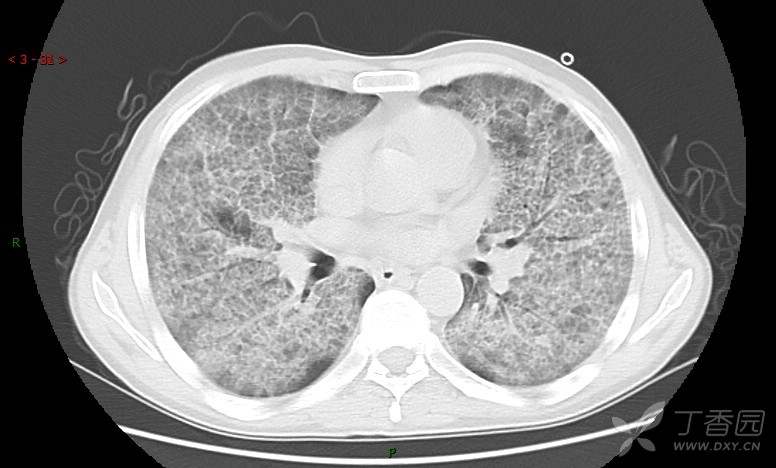

地图+铺路石征=PAP?那升高的CEA怎么说(病例3连发,附其他2例链接)

患者男,42岁,咳嗽半年余,加重伴憋喘2月余。

血清肿瘤相关抗原116.22U/ml↑(0--95);

癌胚抗原 61.96 ng/mL ↑ 0--5

神经特异性烯醇化酶 33.12 ng/ml ↑ 0--16.3

细胞角蛋白19片段测定 40.23 ng/ml ↑ ≤3.3